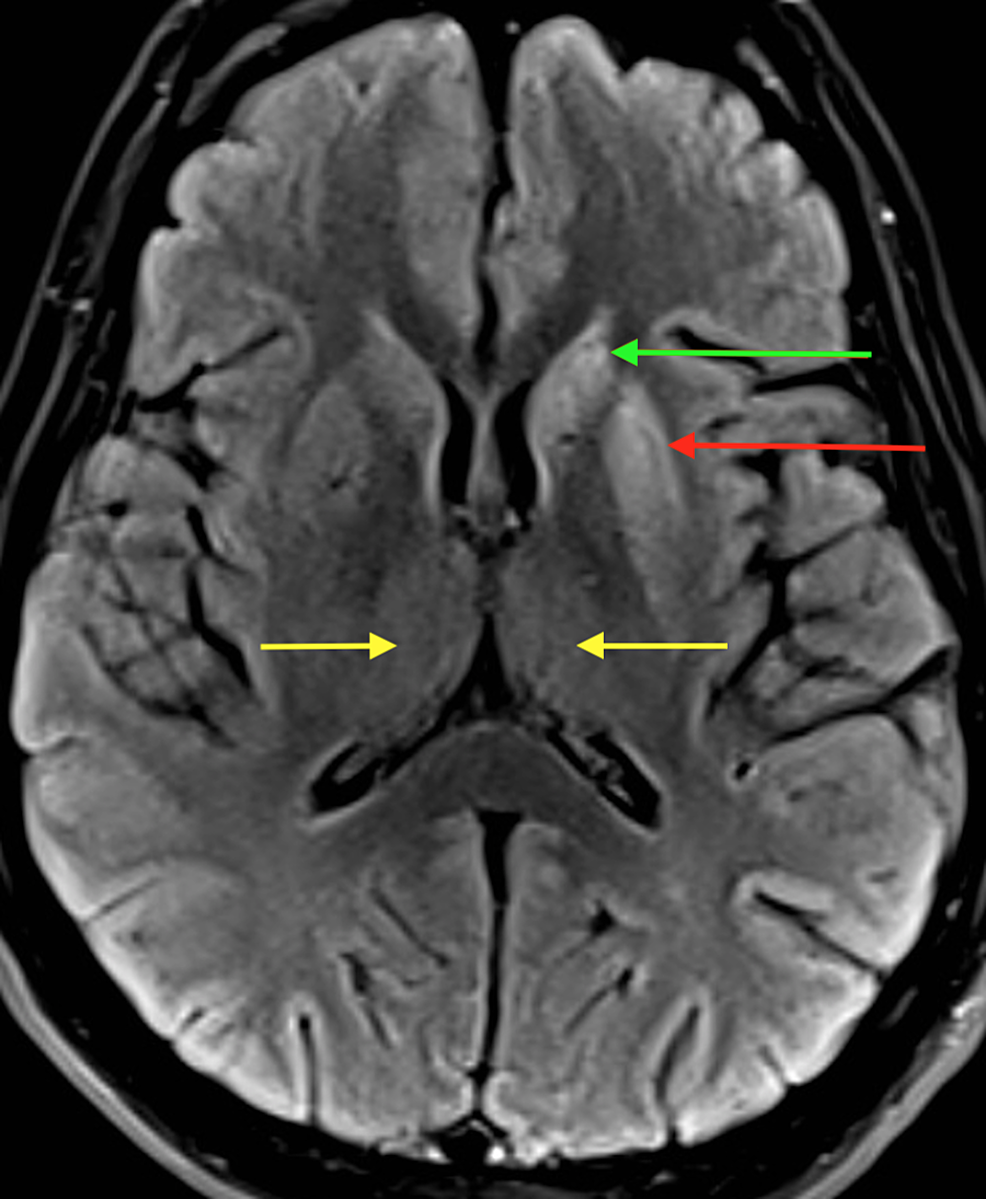

CJD profiles of MRI and EEG from probable CJD patients. (A) Brain MRIs

CJD profiles of MRI and EEG from probable CJD patients. (A) Brain MRIs What Is The Medical Condition Cjd It causes brain damage that worsens rapidly over time. It has severe effects on the brain. Symptoms may take years to appear, and can include rapidly. A brain biopsy or an exam of brain tissue after death, known as an autopsy, is the gold standard to confirm the presence of. It is believed to be. What Is The Medical Condition Cjd.